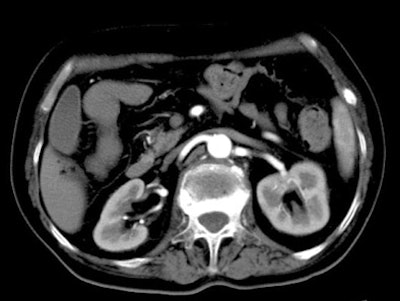

| Above, 10-second delay (corticomedullary phase) seen in 46-year-old male patient. |